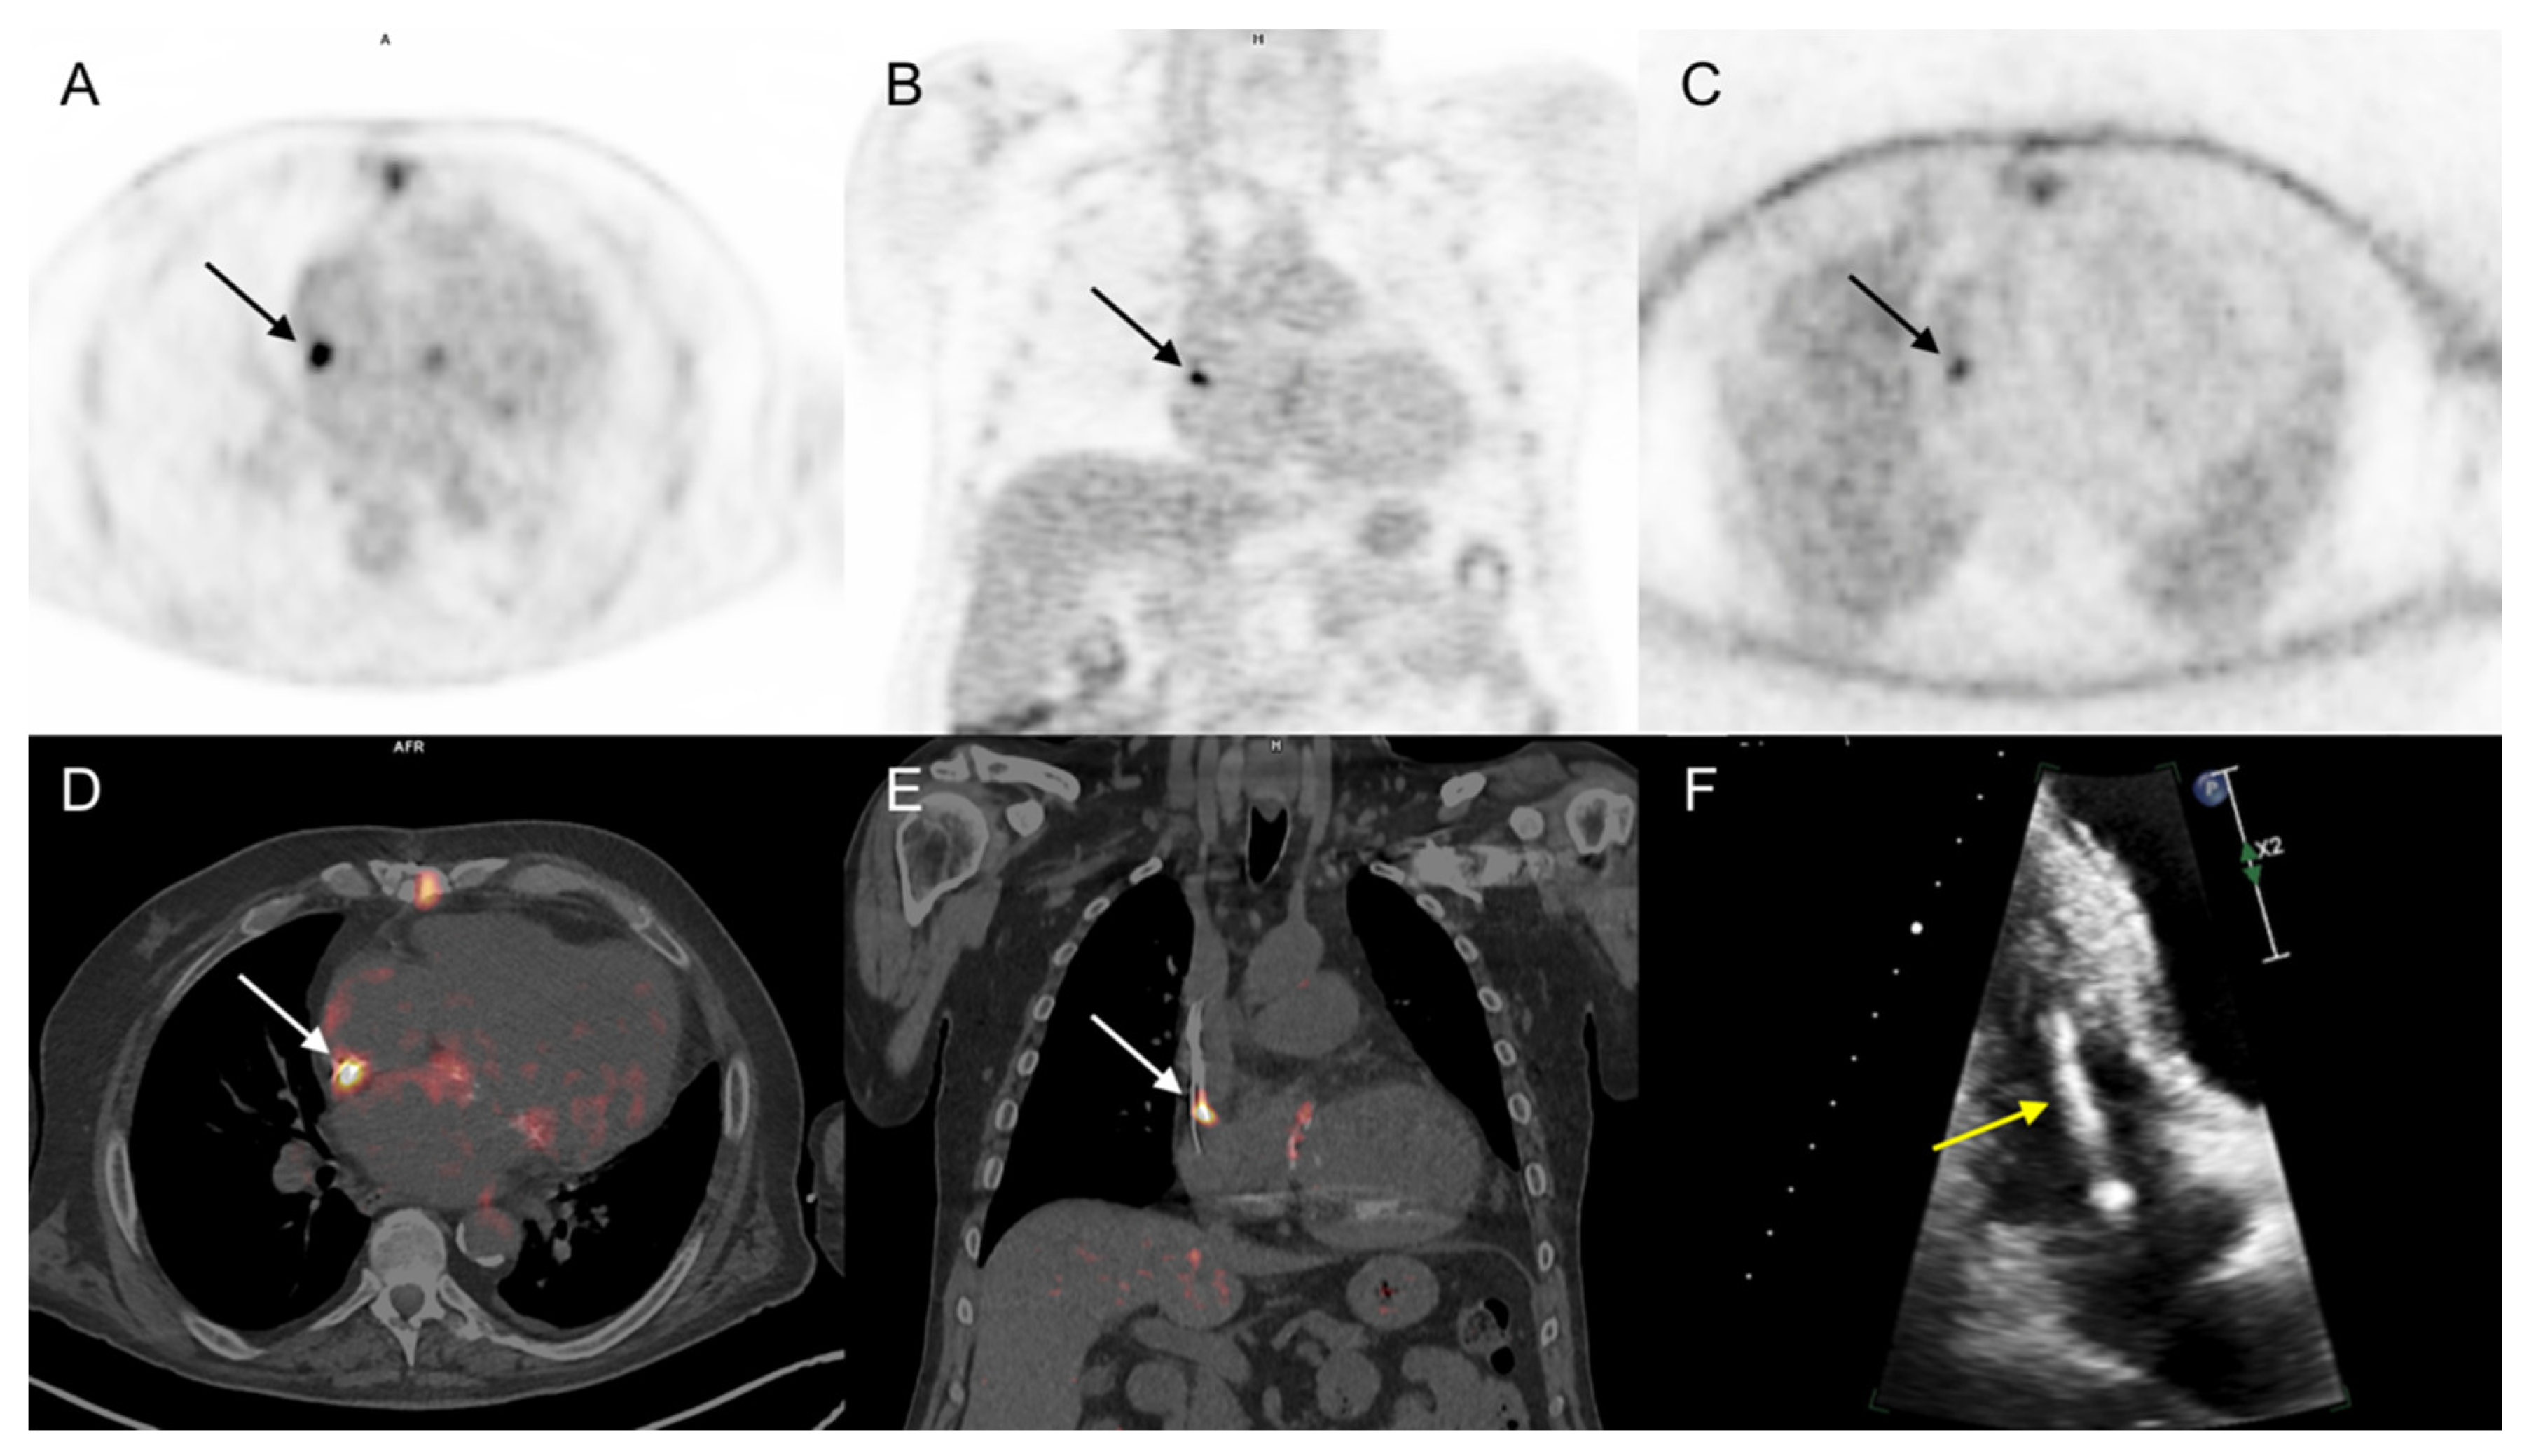

3.3.1. Cardiac Area Investigation

3.3.2. Extra-Cardiac Infection Assessment